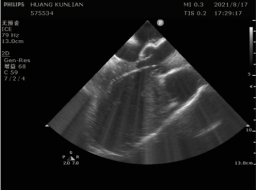

郭军和陈小明借助雅培最新的心腔内超声导管(ViewFlex),将导管放在室间隔部位,通过调整角度清晰观察出左心室两个乳头肌的位置与周围组织的相对关系,实时锁定正在随心脏跳动的乳头肌。

图片附件

红色箭头处为左后乳头肌,白色箭头处为左前乳头肌